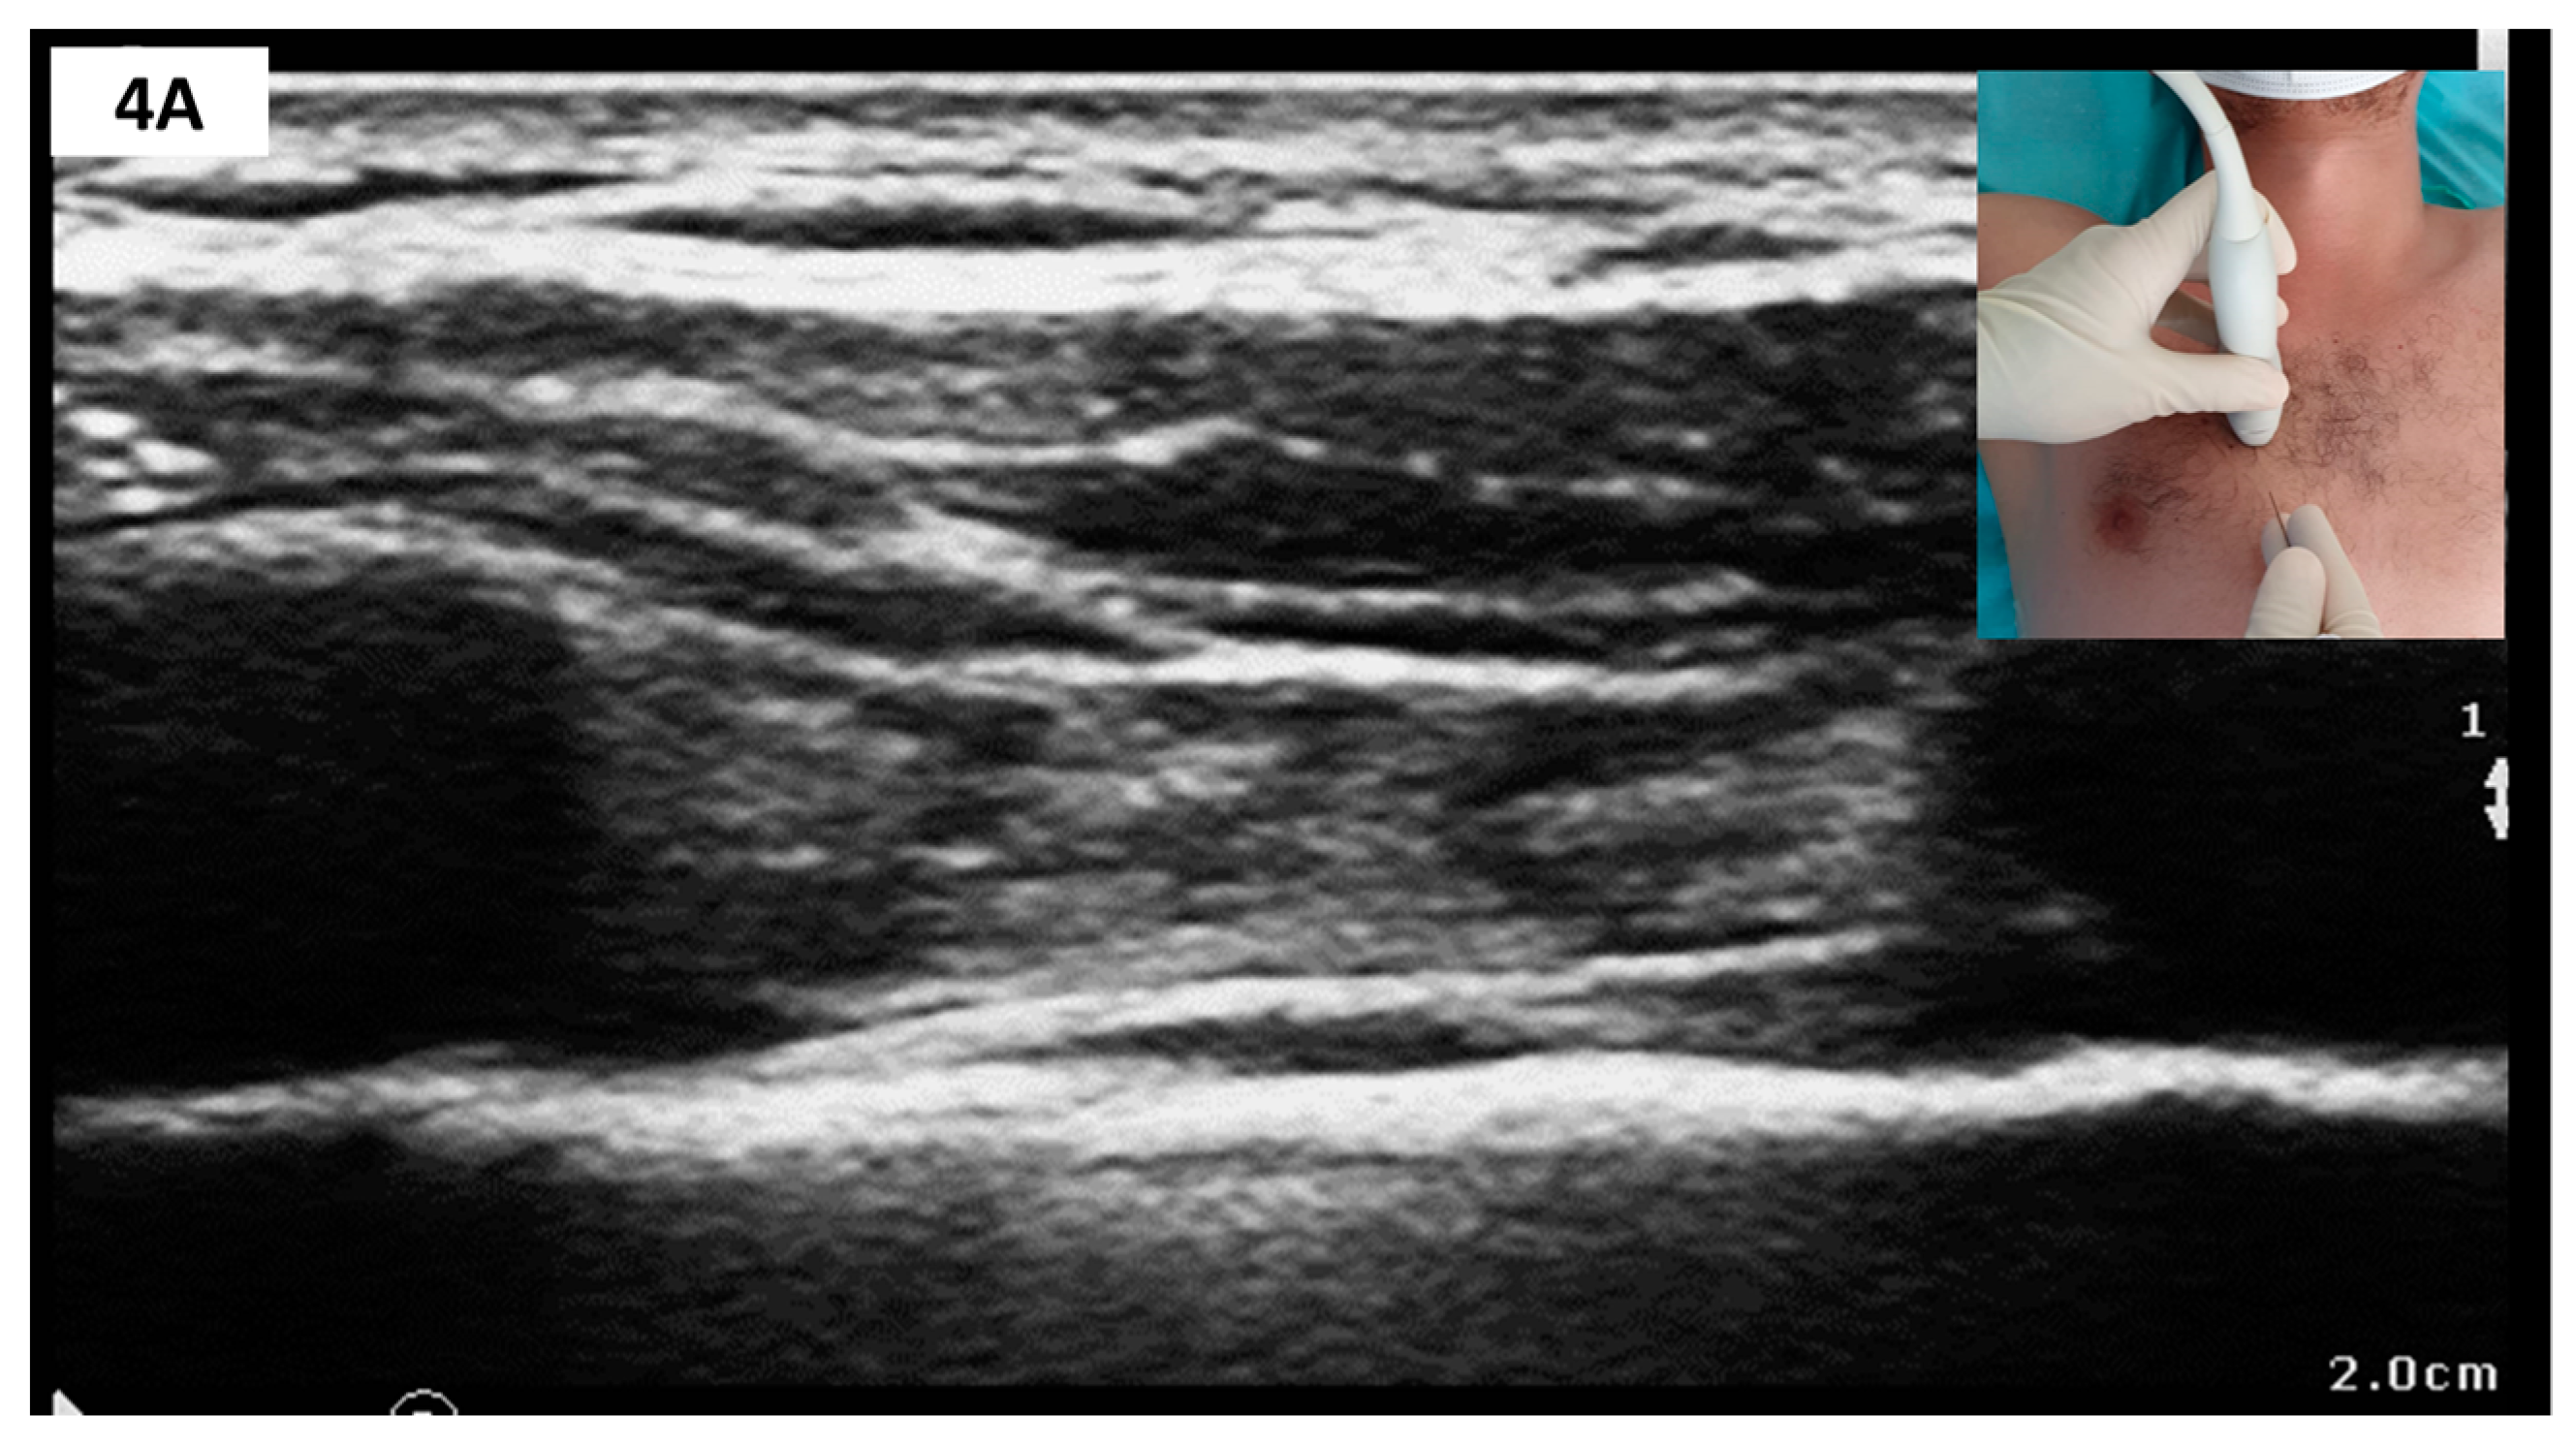

2.3.3. Anteromedial CWFPB—Parasternal Block Variants

Sonoanatomy and Block Technique (Figure 4)